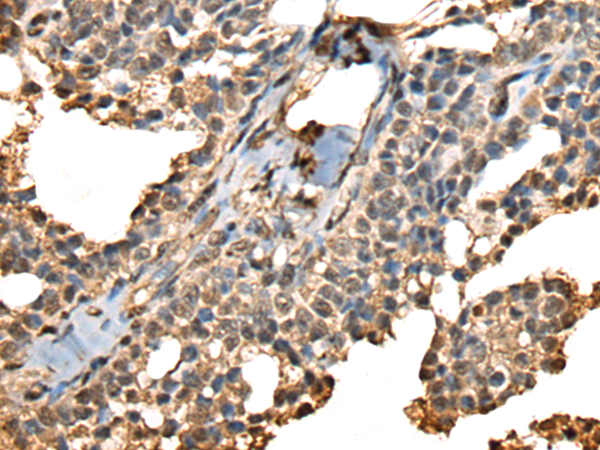

- The image is immunohistochemistry of paraffin-embedded Human ovarian cancer tissue using P02393(PHF21A Antibody) at dilution 1/50. (Original magnification: ×200)